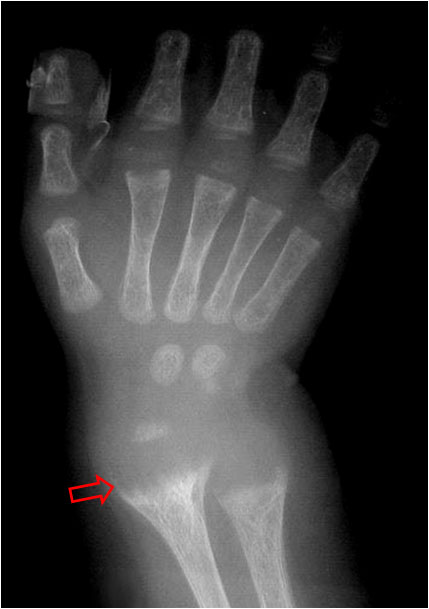

SIGNO DE LA BANDA METAFISARIA DENSA

Aumento de densidad de las metáfisis (flecha) visible en la radiografías convencionales, no acompañado de aplanamiento o deformidad del hueso. Corresponde a una rápida deposición de calcio en las metáfisis que acontece después de varias circunstancias en las que se compromete la osteogénesis. El resultado es el aumento del número y grosor de las trabéculas óseas en las metáfisis.

Este signo puede verse como variante de la normalidad, en las intoxicaciones por plomo u otros metales pesados, en la leucemia tratada, en el hipotiroidismo congénito, en el hiperparatiroidismo y en infecciones transplacentarias (toxoplasmosis, rubéola, citomegalovirus, herpes).